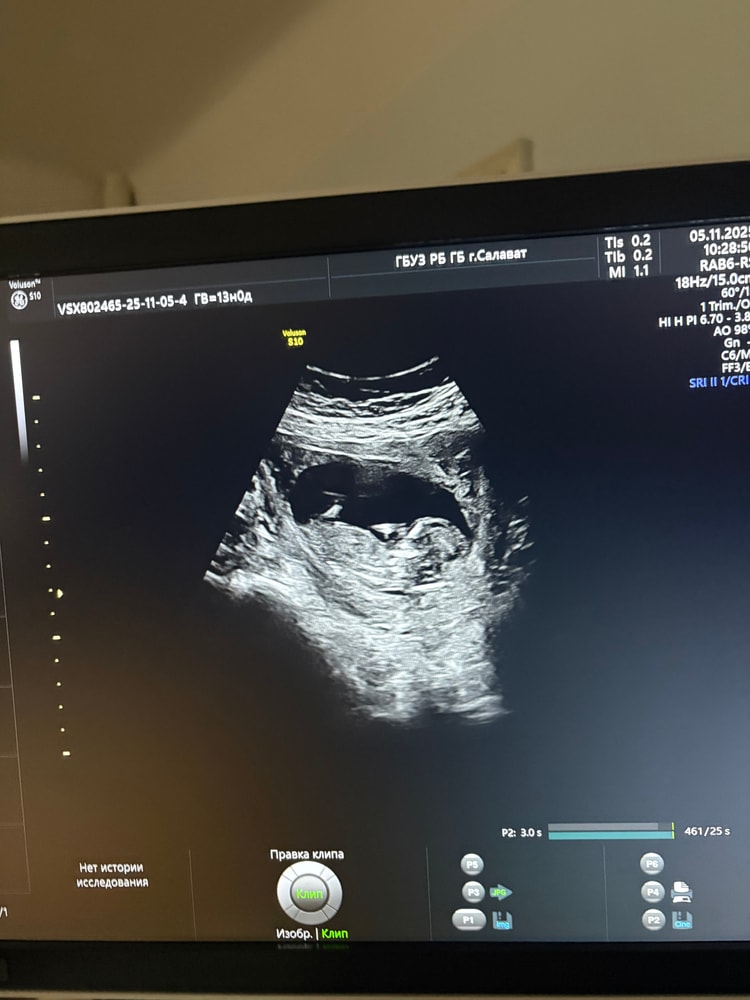

Всем привет! Я тут новенькая, сейчас 13 неделя) жду второго скрининга, очень уж интересно, кто будет 😁 как вы думаете?)